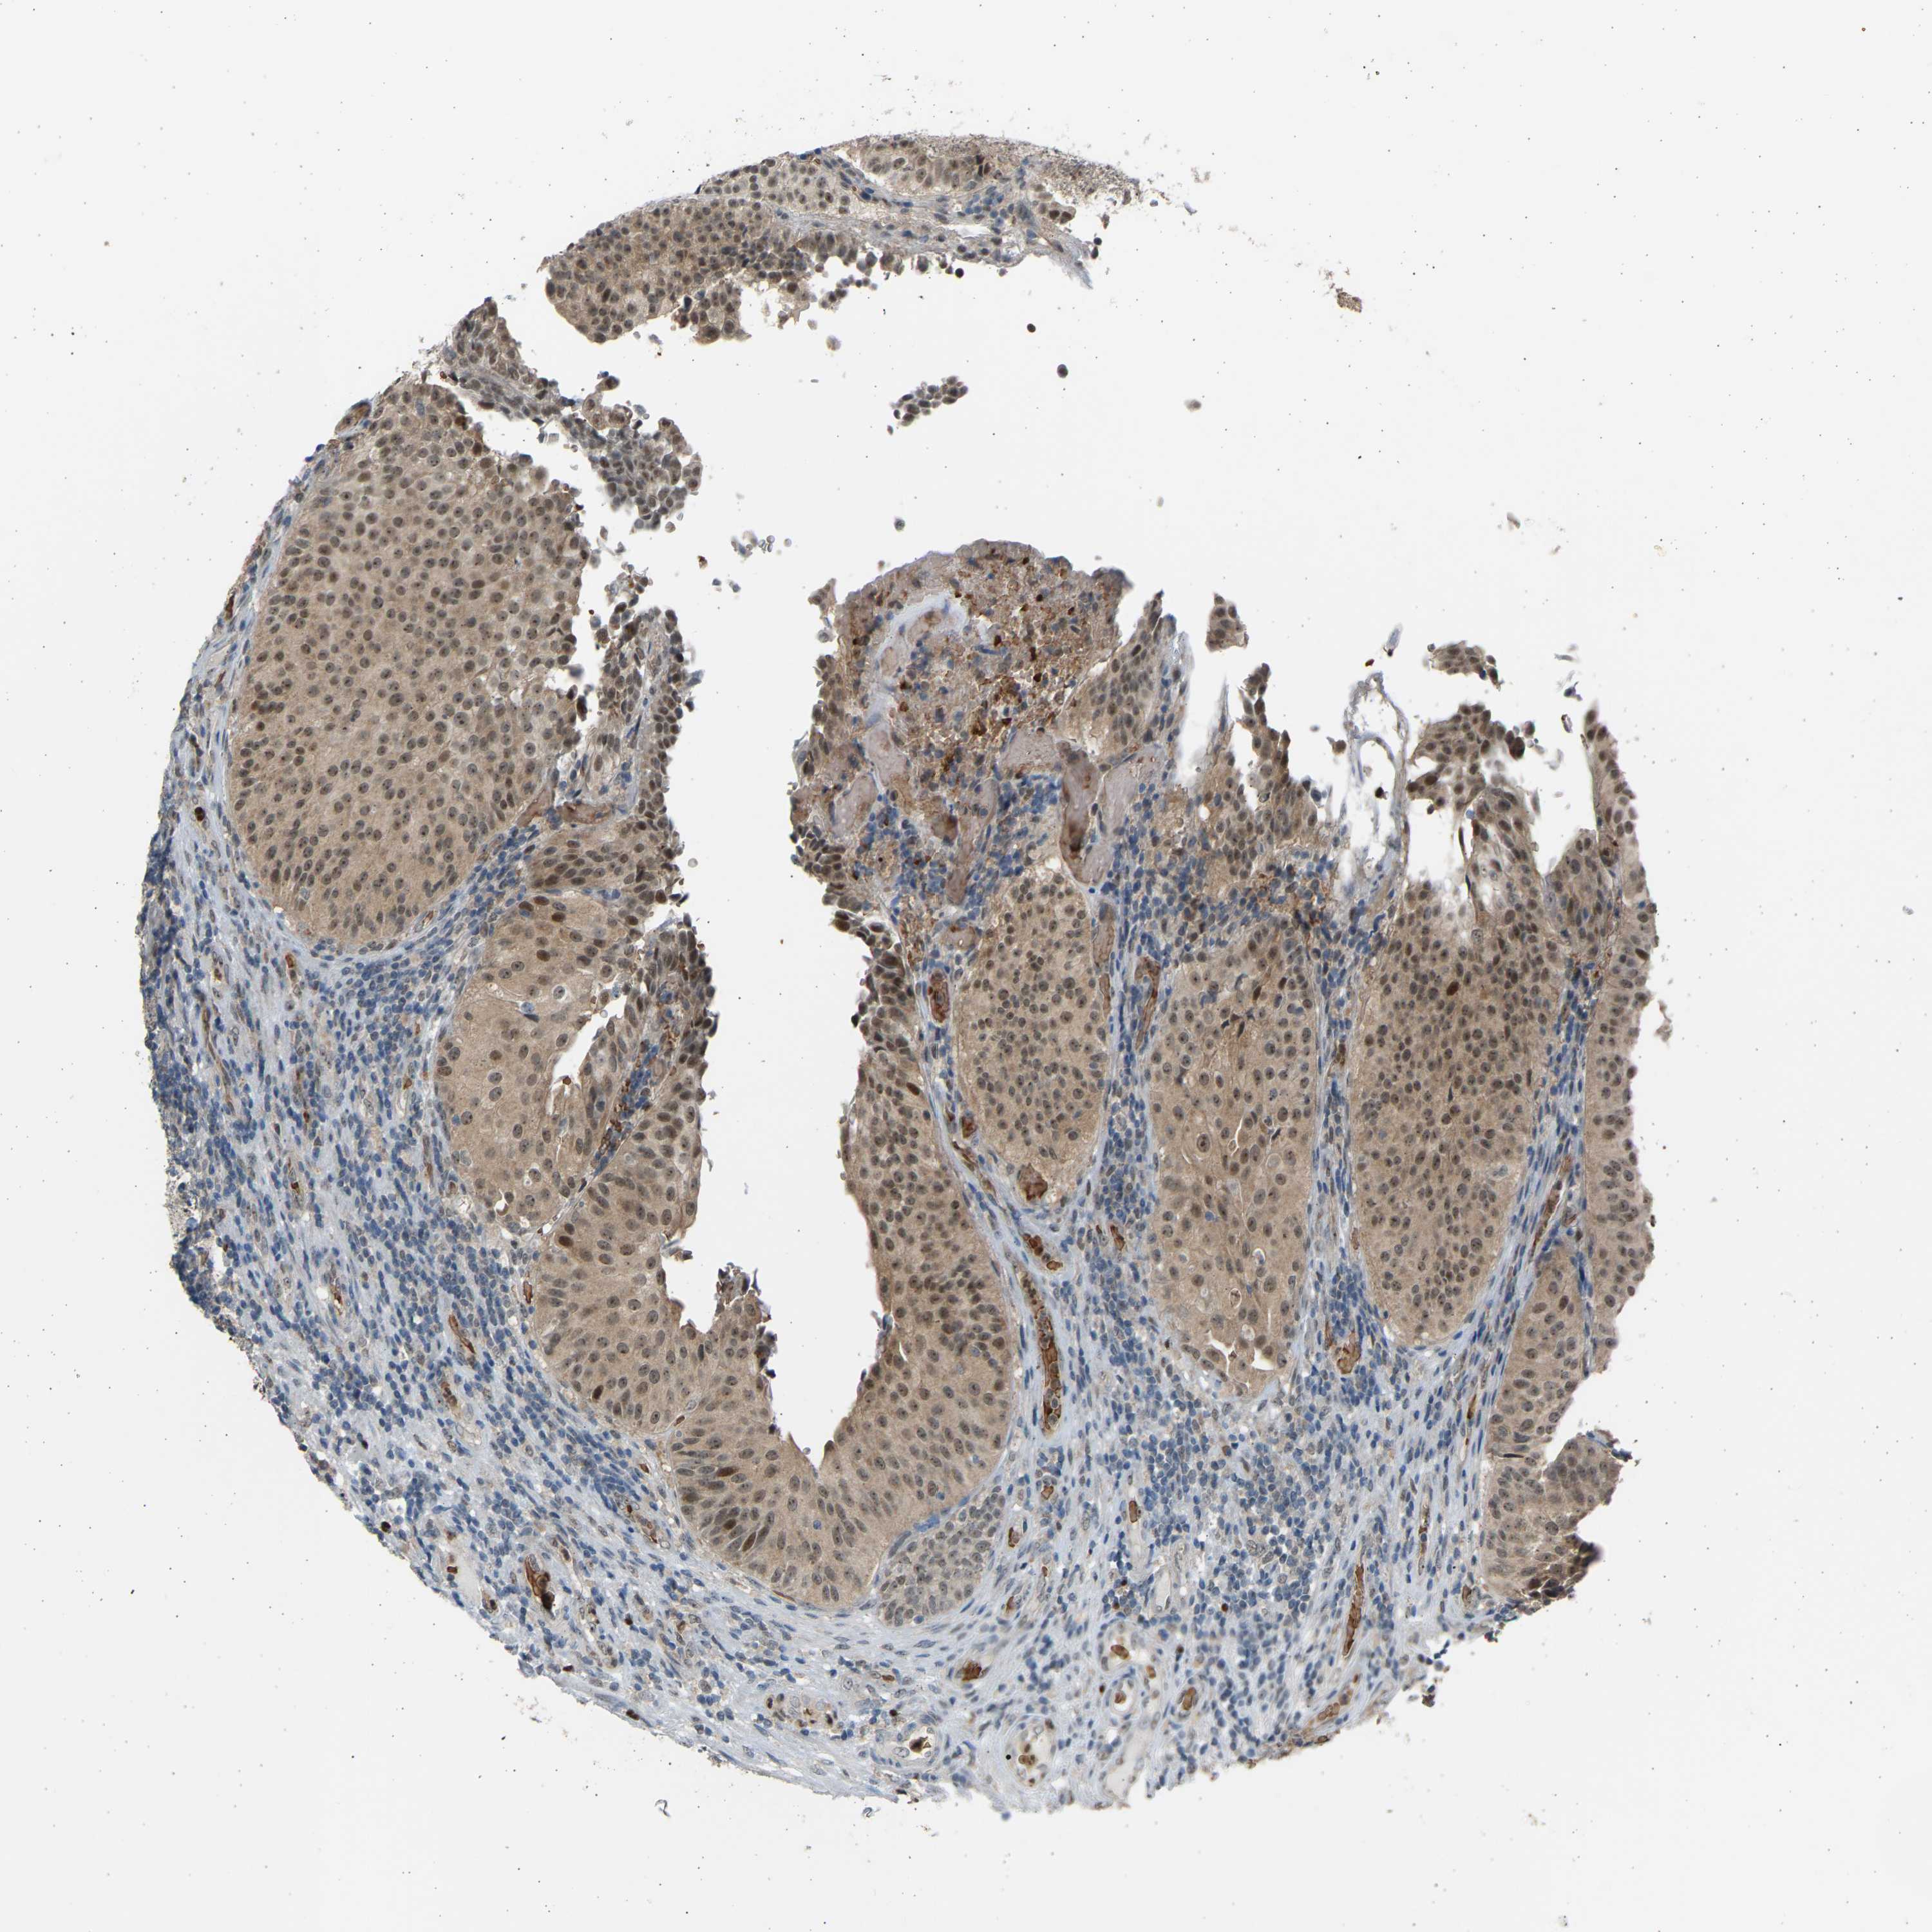

UROTHELIAL CANCER - Protein expressioni

A mouse-over function shows sample information and annotation data. Click on an image to view it in a full screen mode. Samples can be filtered based on level of antibody staining by selecting one or several of the following categories: high, medium, low and not detected. The assay and annotation is described here.

Note that samples used for immunohistochemistry by the Human Protein Atlas do not correspond to samples in the TCGA dataset.

Antibody stainingi

Antibody staining in the annotated cell types in the current human tissue is reported as not detected, low, medium, or high, based on conventional immunohistochemistry profiling in selected tissues. This score is based on the combination of the staining intensity and fraction of stained cells.

Each image is clickable and will lead to virtual microscopy that enables deeper exploration of all samples and also displays staining intensity scores, fraction scores and subcellular localization as well as patient and tissue information for each sample.

Antibody HPA005513

Antibody CAB020661

Urothelial carcinoma, High grade

Urothelial carcinoma, Low grade